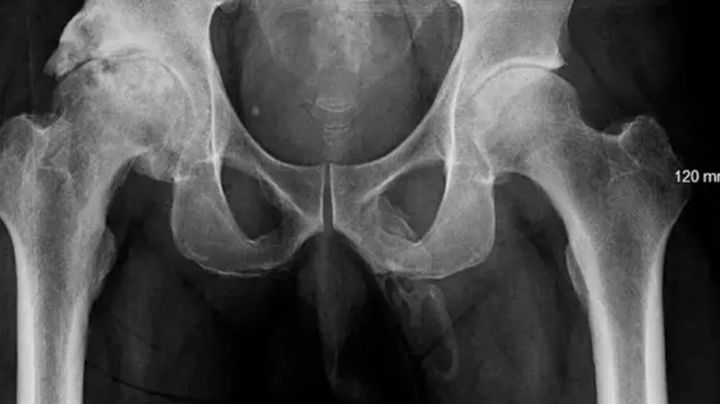

A씨는 초기 진찰에서 무릎 외에는 다른 신체 이상이 없었다. 의료진은 음경의 통증 원인을 찾기 위해 추가 검사를 진행했지만, 외부적인 손상이나 염증, 분비물 등은 전혀 없었고, 전립선 역시 정상 상태로 나타났다. 그러나 골반 X-ray 검사에서 놀라운 사실이 밝혀졌다. 음경 내부에서 뼈와 유사한 단단한 구조물이 확인된 것이다. 이는 음경 내 칼슘 축적이 진행돼 석회화 과정을 통해 조직이 경화된 것으로 나타났다.

뉴욕포스트는 의료진이 A씨의 상태를 음경 골화증으로 의심했다고 전했다. 음경 골화증은 음경 연조직에 칼슘이 쌓여 비골격 구조물이 형성되는 희귀 질환이다. 일반적으로는 특정 부위에 국소적으로 발생하는 경우가 대부분인데, A씨의 사례처럼 음경 전체에 걸쳐 골화가 진행된 경우는 극히 드물다.